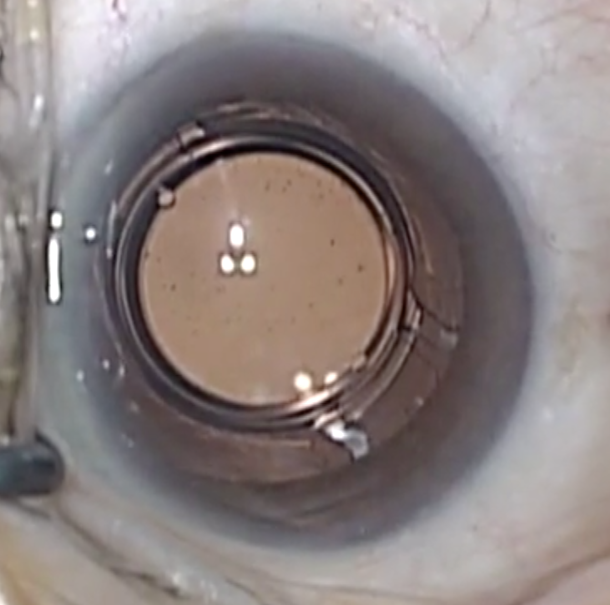

In a well-matched sample group, patients with higher levels of postoperative astigmatism reported a greater improvement in quality of life and a greater rate of willingness to have the procedure again if they received an Extended Depth of Focus IOL compared to patients receiving a low-add, multifocal IOL, despite similar postoperative clinical and patient reported performance.